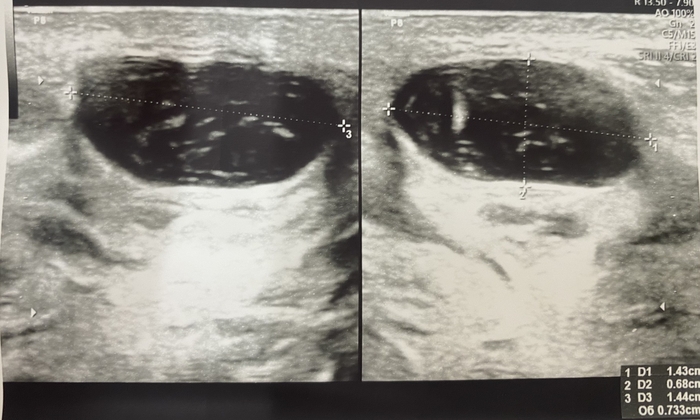

Поликистоз почек⁠⁠

Поликистоз почек

Поликистоз наследственное заболевание - является распространенным заболеванием, встречающимся примерно у 1 из 1000 живорожденных. Предполагается, что менее половины этих случаев будут диагностированы в течение жизни пациента, поскольку заболевание часто протекает клинически бессимптомно.